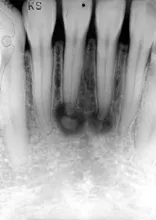

Case 11

The problem: Radiographic examination revealed mixed lucent-opaque lesions around the apices of teeth #24 and #25.

Periapical cemento-osseous dysplasia